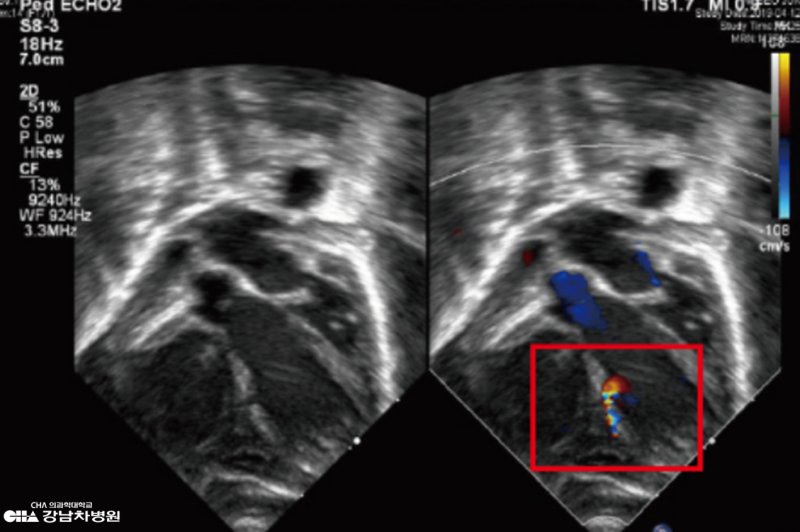

선천성횡격막탈장(D+236)_서울아산병원 소아외과 외래, 소아심장초음파검사